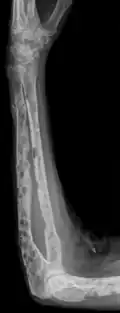

X-ray of the forearm, with lytic lesions -

The diagnostic examination of a person with suspected multiple myeloma typically includes a skeletal survey. This is a series of X-rays of the skull, axial skeleton, and proximal long bones. Myeloma activity sometimes appears as "lytic lesions" (with local disappearance of normal bone due to resorption) or as "punched-out lesions" on the skull X-ray ("raindrop skull"). Lesions may also be sclerotic, which is seen as radiodense.[76] Overall, the radiodensity of myeloma is between −30 and 120 Hounsfield units (HU).[77] Magnetic resonance imaging is more sensitive than simple X-rays in the detection of lytic lesions. An MRI may supersede a skeletal survey, especially when vertebral disease is suspected. Occasionally, a CT scan is performed to measure the size of soft-tissue plasmacytomas. Nuclear Medicine Bone scans are typically not of any additional value in the workup of people with myeloma (no new bone formation; lytic lesions not well visualized on nuclear bone scan).

Bone pain affects almost 70% of people with multiple myeloma and is one of the most common symptoms.[2]: 653 [23] Myeloma bone pain usually involves the spine and ribs and worsens with activity. Persistent, localized pain may indicate a pathological bone fracture. Involvement of the vertebrae may lead to spinal cord compression or kyphosis. Myeloma bone disease is due to the overexpression of receptor activator for nuclear factor κ B ligand (RANKL) by bone marrow stroma. RANKL activates osteoclasts, which resorb bone. The resultant bone lesions are lytic (cause breakdown) in nature. They are best seen in plain radiographs, which may show "punched-out" resorptive lesions (including the "raindrop" appearance of the skull on radiography). The breakdown of bone also leads to the release of calcium ions into the blood, leading to hypercalcemia and its associated symptoms.[24]